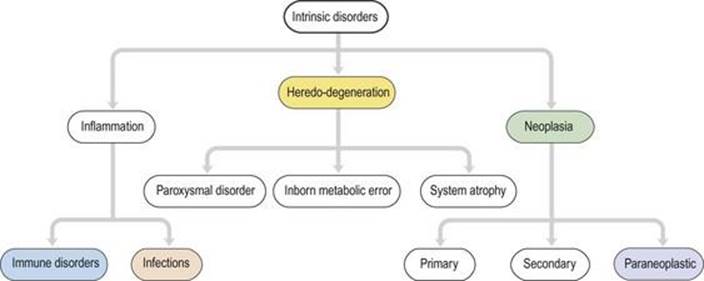

اختلالات سیستم عصبی عضلانی چهار نوع عمده هستند (شکل ۱.۳۰) در رابطه با علت یا علت.

شکل ۱.۳۰ چهار دسته عمده اختلالات سیستم عصبی عضلانی.

شکل ۱.۳۰ چهار دسته عمده اختلالات سیستم عصبی عضلانی.

اختلالات درونی

اختلالات درونی (شکل ۱.۳۴) اختلالات اولیه خود سیستم عصبی هستند. اختلالات عصبی اولیه درونی ناشایع و اغلب مزمن و غیرقابل برگشت هستند، به طوری که میتوان یک سری تحقیقات آرامتر را انتخاب کرد. بسیاری از اختلالات عصبی تحت تأثیرات ژنتیکی قرار دارند (هرادو-دژنراسیون). خطاهای ذاتی متابولیسم منجر به ناهنجاری ذهنی و ناتوانی در کودکان میشود و معمولاً ناشی از کمبود آنزیمهای خاص است. اختلالات حمله ای شامل از دست دادن اپیزودیک هوشیاری (صرع)، خواب زیاد (نارکولپسی) و سردرد (میگرن) است. انحطاط سیستم (شکل ۱.۳۵) در جوانی و پیری رخ میدهد و منجر به مرگ زودرس (آتروفی) برخی از اجزای عصبی عضلانی، با صرفه جویی در سایر اجزا میشود. هنگامیکه انحطاط سیستم در جوانی رخ میدهد، اغلب یک علت ارثی یا ژنتیکی آشکار دارد: به عنوان مثال، دیستروفیهای عضلانی، نوروپاتیهای حسی حرکتی ارثی، پاراپارزی اسپاستیک ارثی، آتاکسیهای مخچه و بیماریهانتینگتون. هنگامیکه آنها در اواخر زندگی رخ میدهند اغلب پراکنده هستند: به عنوان مثال بیماری نورون حرکتی، بیماری پارکینسون و بیماری آلزایمر.انحطاط سیستم به طور قابل ملاحظه ای انتخابی هستند. به عنوان مثال، در بیماری نورون حرکتی فلج عضله وجود دارد اما هیچ اختلالی در حس وجود ندارد، در حالی که در بیماری آلزایمر، فراموشی شدید اما فلج وجود ندارد.

اختلالات درونی شامل انحطاط سیستم (آتروفی)، خطاهای ذاتی متابولیسم، اختلالات حمله ای، نئوپلاسمها، عفونتها و اختلالات ایمنی است.

نئوپلازی به رشد بیش از حد و کنترل نشده بافتها اشاره دارد که یک تومور خوش خیم یا بدخیم را تشکیل میدهند. نئوپلاسمهای اولیه در خود بافتهای عصبی عضلانی ایجاد میشوند (شکل ۱.۳۶). نئوپلاسمهای ثانویه در گردش خون از سایر مکانهای اندام اولیه (مانند ریه یا سینه) پخش میشوند. به ندرت، تومورها در مکانهای دور توسط مکانیسمهای هومورال یا ایمنی به سیستم عصبی آسیب میرسانند و اختلالات ناشی از آن سندرمهای غیر متاستاتیک یا پارانئوپلاستیک نامیده میشوند (شکل ۱.۳۷).

التهاب بافت عصبی عضلانی ممکن است ناشی از عفونت توسط میکروارگانیسمها باشد (شکل ۱.۳۸) و میتواند ساختارهای مختلفی را تحت تاثیر قرار دهد: به عنوان مثال مننژها (مننژیت مننگوکوکی)، مغز (آنسفالیت ویروسی، نوروسیفلیس) یا اعصاب محیطی (جذام). متناوبا، التهاب میتواند در اختلالات ایمنی رخ دهد (شکل ۱.۳۹)، در غیاب عفونت. شایع ترین اختلال سیستم ایمنی CNS، مولتیپل اسکلروزیس است. اختلالات ایمنی ممکن است به اعصاب محیطی نیز ضربه بزند (نوروپاتی التهابی حاد یا سندرم گیلن – باره).اتصال عصبی عضلانی (میاستنی گراویس) یا ماهیچه (پلی میوزیت). اختلالات التهابی با آزمایشات میکروبیولوژیکی و سرولوژیکی خون و CSF بررسی میشود. درمان عفونت با عوامل ضد میکروبی و سرکوب پاسخهای ایمنی توسط داروهایی مانند کورتیکواستروئیدها ممکن است این بیماریهای عفونی یا ایمنی را درمان یا کنترل کند.